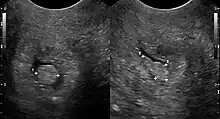

![]() | |

| Cervical polyp on ultrasound | |